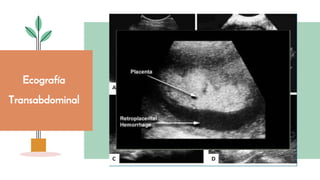

● Nosinformasobrelaubicacióndelaplacenta.

● Útilparavalorarloshematomasplacentarios.

● Sensibilidaddel25-50%(ausenciadehallazgosnodescartaDPPNI)

● Desventaja:laplacentaycoágulosfrescospuedentenercaracterísticas

similares.

Ecografía

Transabdominal